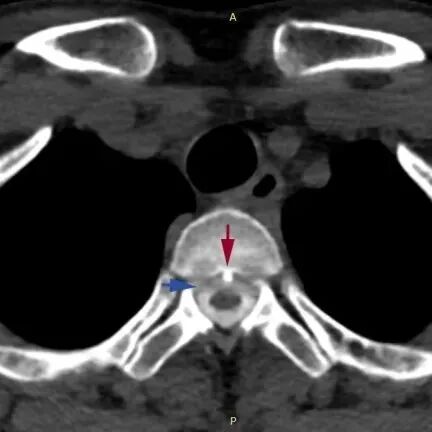

患者的脊柱磁共振檢查,可見第2、3胸椎之間有“骨刺”形成,刺破硬脊髓膜,造成腦脊液外漏。